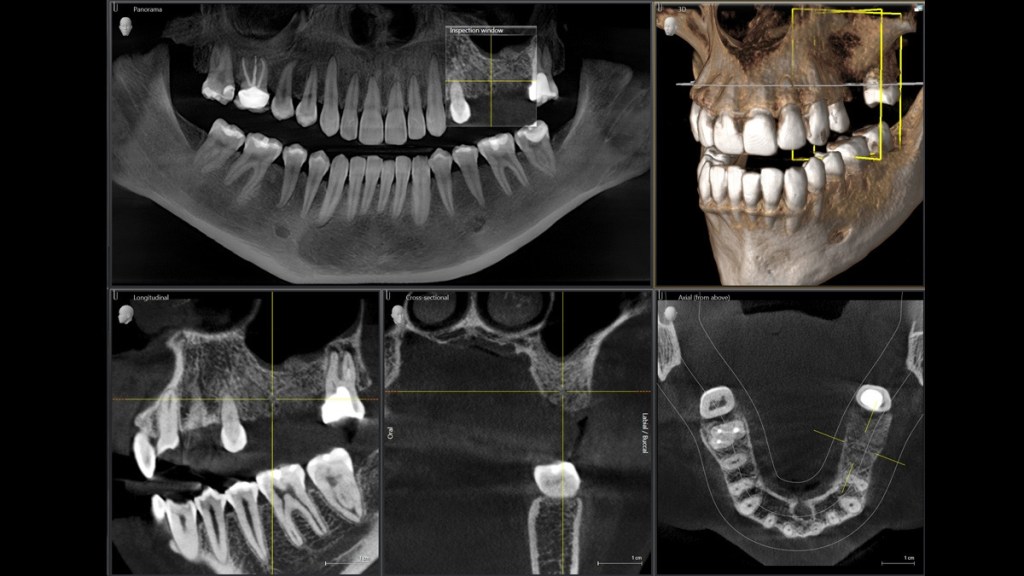

3D (CBCT) TEHNOLOGIJA

Napretkom tehnologije, razvila se potreba za snimcima koji su precizniji i detaljniji, ali i smanjenom dozom zračenja u odnosu na tradicionalni skener. Tako je nastao CBCT (Cone Beam Computed Tomography), koji koristi princip rada standardnog skenera, ali uz znatno manju dozu zračenja.

Danas je najviše zastupljen u stomatologiji, ali ga često koriste specijalisti ORL. Prednost u odnosu na standardne (ortopan i dental) snimke je što se snimak radi u sve tri dimenzije, tako da ne postoji mogućnost superpozicije. Aparat u određenom radnom polju, čini veliki broj presjeka, u sve tri dimenzije. Veličina radnih polja omogućava savršen prikaz u zavisnosti od zone interesovanja. S polje ili Malo radno polje (6×6 cm) je namenjeno za planiranje zahvata u jednom sekstantu ili kvadrantu (hiruški zahvati sa pojedinačnim implantima, lokalizovani dentalni problemi). M polje ili Srednje polje (7,5×10 cm) pogodno je za pregled čitavog dentalnog aparata uključujući i f.mandibularis i f.mentalis. Ovo radno polje može obuhvatiti oba zubna luka, sa podom maksilarnog sinusa kao i mandibularnim kanalom. Ovo polje je takođe korisno za implantološko planiranje. Bitno je imati na umu da su S i M radno polje “podesivi”, i nisu fikso određeni, samo je bitno naglasiti našem rendgen tehničaru zonu interesovanja (npr. M polje može zahvatiti kompletan maksilarni sinu i gornj zubni luk, ako nije potrebno snimati donje zube). L i XL ili Velika polja (7,5×14,5 cm / 10×14,5 cm) idealna su kada je potrebno napraviti pregled obe vilice. Na snimku su prikazani i TM zglobovi, gornji deo cervikalne kičme. Obuhvataju cjelokupnu dentomaksilofacijalnu oblast, prosirujuci dijagnosticke i planirajuce tretmane za ortodontske procedure, koriste se i za analizu fraktura kostiju lica, kao i za studije vazdušnih puteva. Osim velikog broja preseka, softver u kom se obrađuju snimci OnDemand 3D, posjeduje u sebi veliki broj pomoćnih alatki/pomagala: mjerenja u sve tri dimenzije, virtualno planiranje implanata, virtualna rekonstrukcija disajnih puteva, itd. Uslijed velikog broja presjeka koje ovaj snimak posjeduje štampanje bi bilo neisplativo, stoga se ovi snimci režu na CD-ove, ili šalju putem WeTransfera, na željenu e-mail adresu stiže link za preuzimanje snimka.